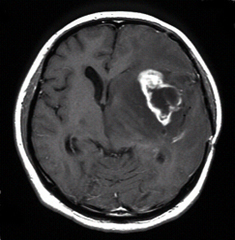

ところが、最近少しずつ状況が好転してきました。平成18年、欧米を始め世界各国ではすでに悪性神経膠腫の標準薬として使用されていたテモゾロミドが、我が国でも承認されました。この抗癌剤は飲み薬ですが従来の注射薬と比べても治療効果が高く、2年生存率を3倍に伸ばすという効果が実証されています。図1の患者さんは、手術・放射線や他の薬剤を使用した化学療法でも腫瘍の進行を全く止めることが出来なかったのですが、テモゾロミドを4コース使用した後に、腫瘍が完全に消失しました。この患者さんはその後3年間にわたって再発がありません。

図1:悪性脳腫瘍に対するデモゾロミドの効果

投与前